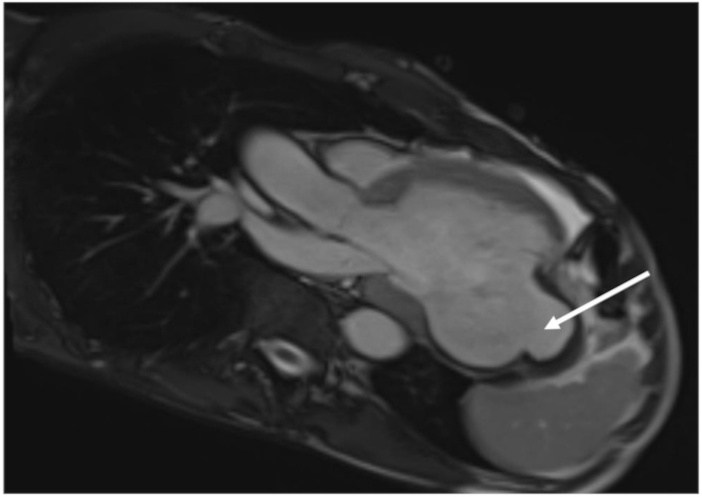

He underwent a right and left heart catheterization, which demonstrated 70% stenosis of his first diagonal vessel, 90% stenosis of his second diagonal vessel, and a second marginal artery, which was fully occluded at its ostium. Finally, a CMR was obtained, which was consistent with a large pseudoaneurysm measuring 8 × 7 × 5 cm containing lateral wall rupture (Figure 1, Figure 2, Figure 3). Within the pseudoaneurysm, a mural thrombus was present, measuring 2 cm in thickness.

Cardiac MRI three chamber view-vertical long axis. Large left ventricular pseudoaneurysm noted.